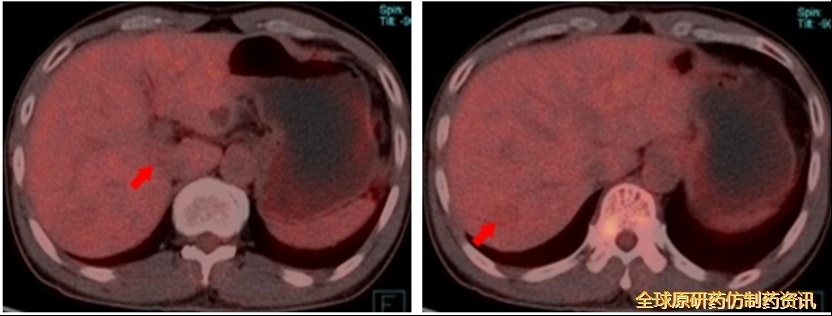

首次消融术后45个月复查(即第三次消融术后20个月,2021.07)

AFP 5638 ng/mL;

MRI增强见肝Ⅸc段强化结节,考虑肝Ⅸc段肿瘤复发。

图9 MRI增强检查结果

第四次消融(2021.07.28)

CT消融过程中,消融针从门-腔间隙穿透肿瘤;

消融毕,术区呈条状密度增高灶,相邻胆管、血管无扩张、积气。

图10 第四次消融示意图

第四次消融术后1个月复查(2021.08)

术后1月余,肝Ⅸc段术区消融彻底,未见异常强化灶。

图11 MRI复查结果